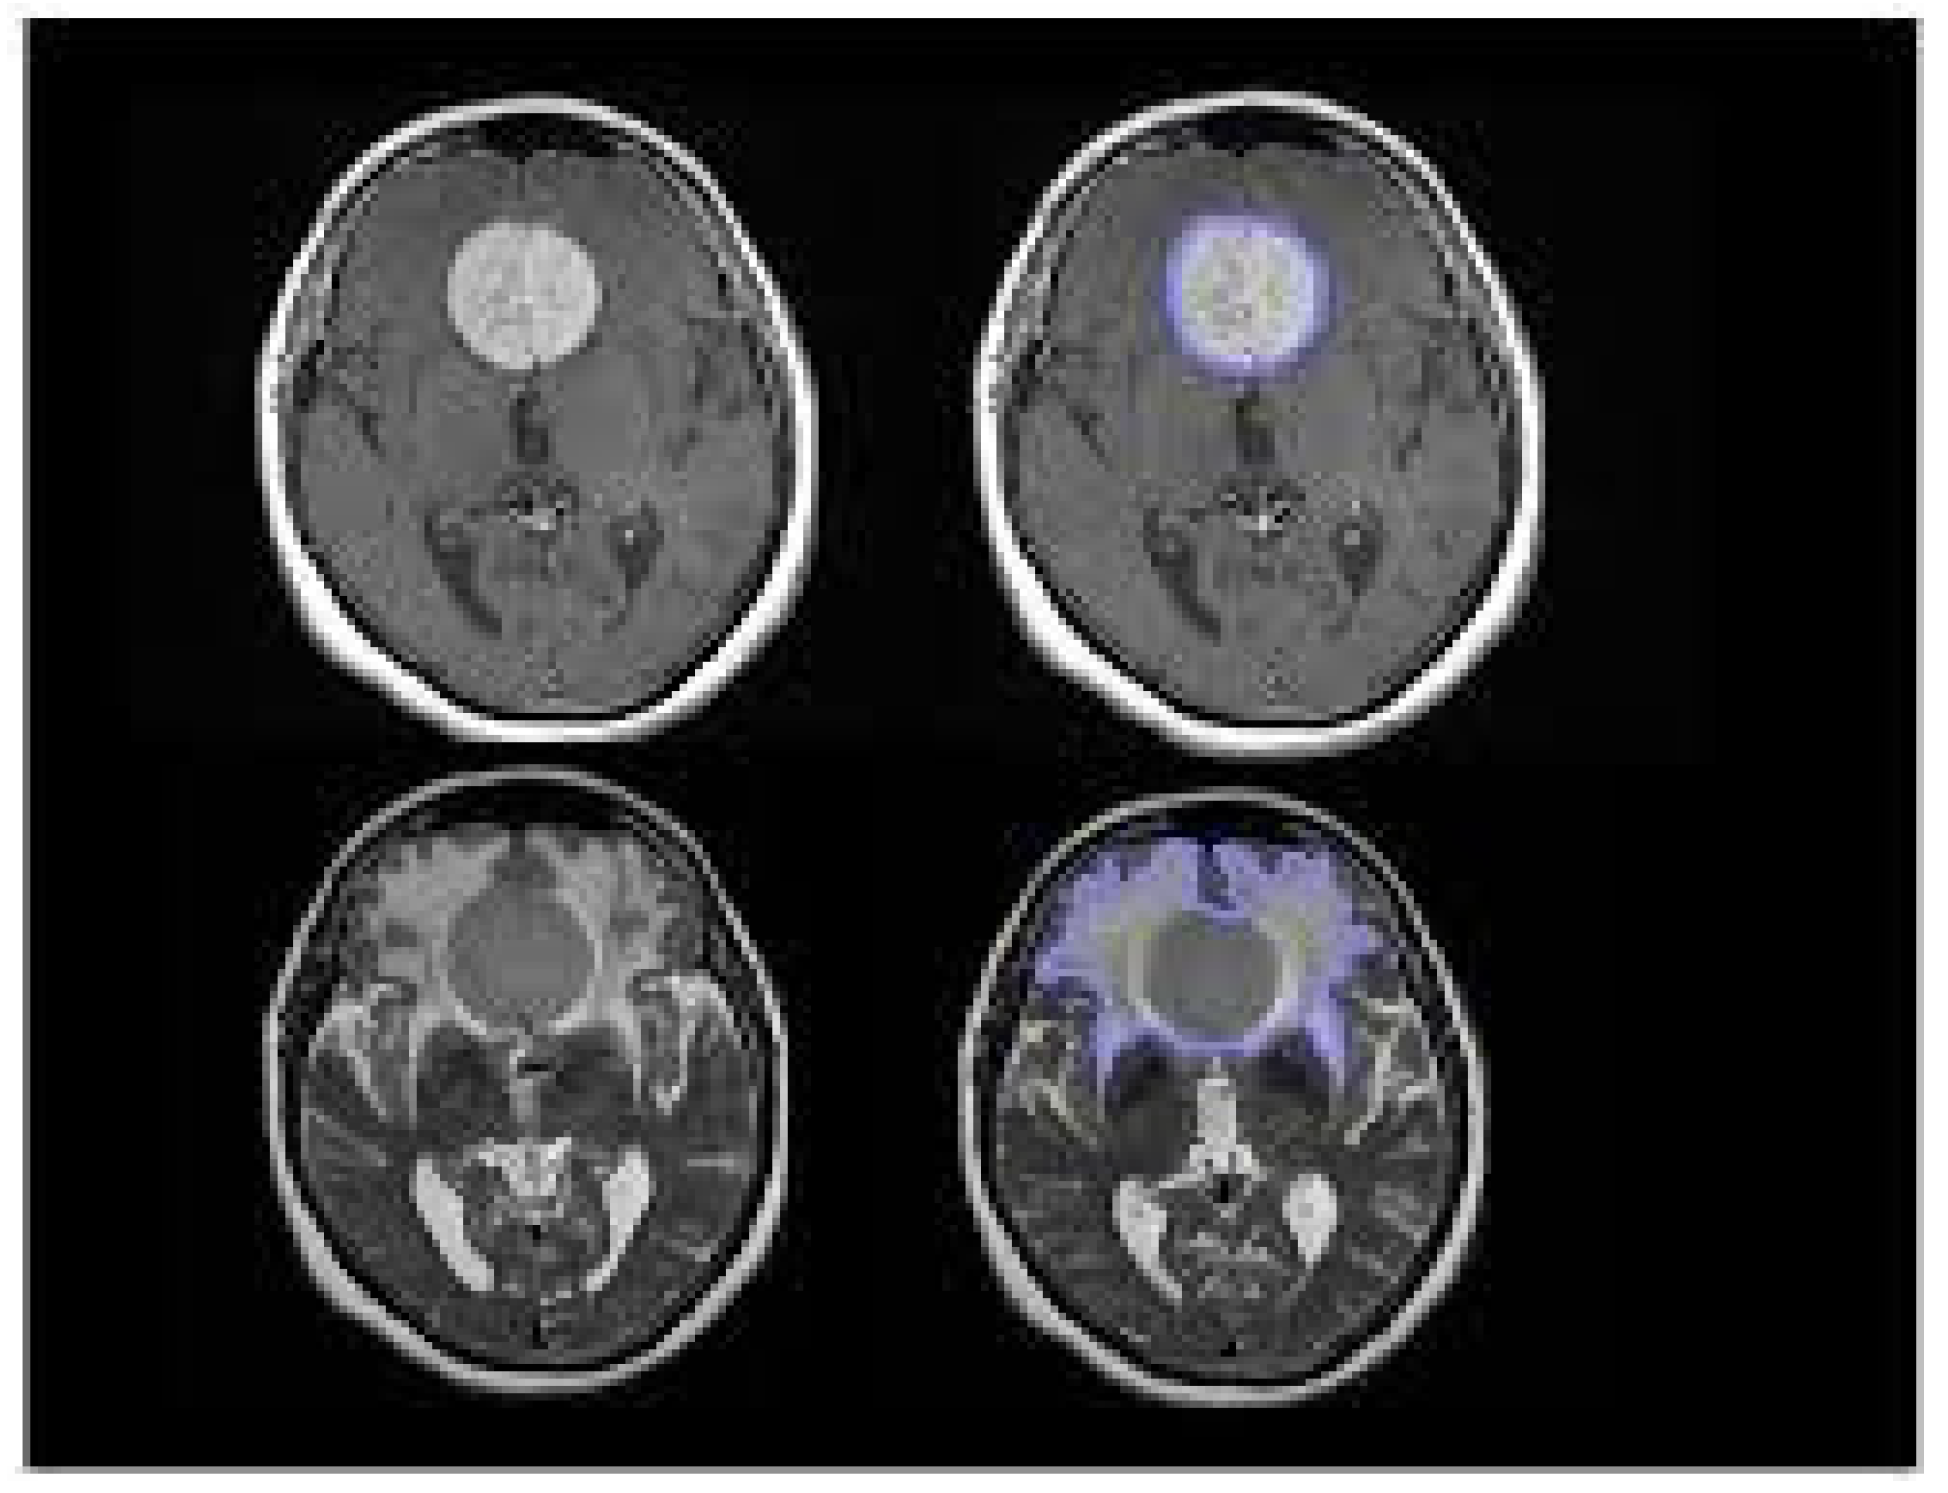

Enhanced lesion on 3D T1-weighted sequences and to identify its relative hyperintense signal on T2-weighted sequences using Horos software [30].

Preprints 77552 g001